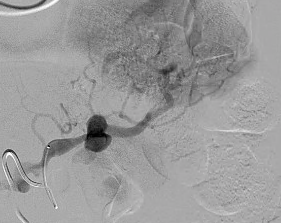

@dpduncanMD_IR @VUMCradiology @UCSDRadRes @Quinn_Meisinger @myliuMD @shelbyfrantzMD @iRadRock @MinaMakaryMD @theIIMD @IRdocAndy @JohnDoIR @RmelikMD @TWongMD @DRimaniIR @danbrownIO @ecemmons @CBoonie_nanoIR @Ajairam_MD_IR pubmed.ncbi.nlm.nih.gov/35907643/ I’ve always thought this was a great case. Great technique by the IR to boot!